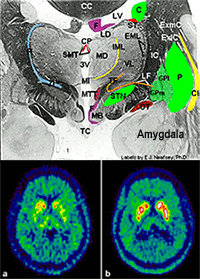

TOP : Highly detailed slide of human brain tissue taken post-mortem.

BOTTOM : F-dopa PET in Parkinson's disease before (a) and after (b) dopamine cell implantation